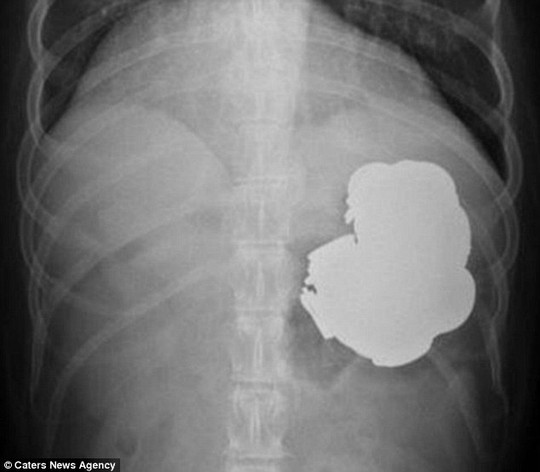

Dị vật kim loại trong cơ thể bệnh nhân

Tuy nhiên, kết quả nội soi và X- quang khiến bác sĩ hết sức kinh ngạc: Người đàn ông đã nuốt hàng trăm đồng tiền xu, đinh vít và móng tay. Theo lời bệnh nhân, trong khoảng 3 năm, Rajpal Singh đã nuốt tổng cộng 140 đồng xu, 150 đinh vít cùng các loại hạt, bu lông, móng tay, pin, nam châm…

Ngay sau đó, các bác sĩ đã phẫu thuật nội soi trong 9 giờ để gắp 240 vật lạ từ dạ dày người đàn ông.

Bác sĩ Goyal cho hay: “Bệnh nhân nhập viện trong tình trạng đau bụng dữ dội. Sau khi nội soi, chúng tôi đã sốc khi nhìn thấy nhiều dị vật, bao gồm tiền xu và những vật sắc nhọn trong bụng anh ta. Mặc dù đã cố gắng gắp hầu hết dị vật nhưng vẫn có một số đồng tiền xu, vật sắc nằm sâu trong đó chúng tôi chưa thể gắp ra”.